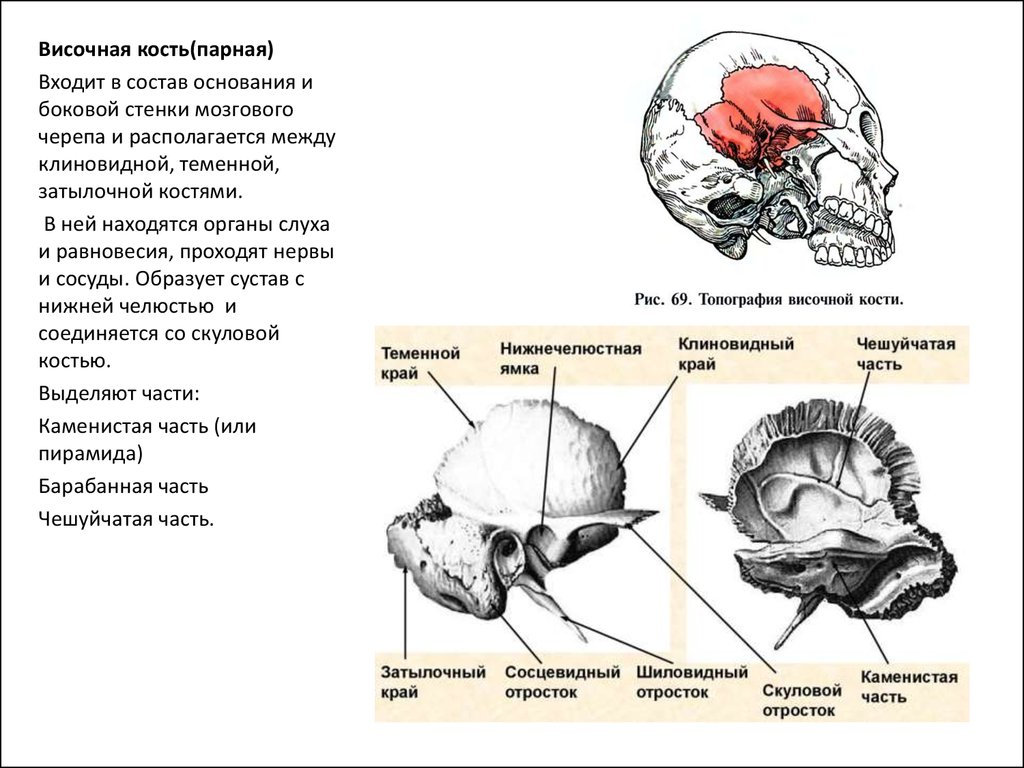

КТ анатомия сосцевидного отростка: особенности и показания